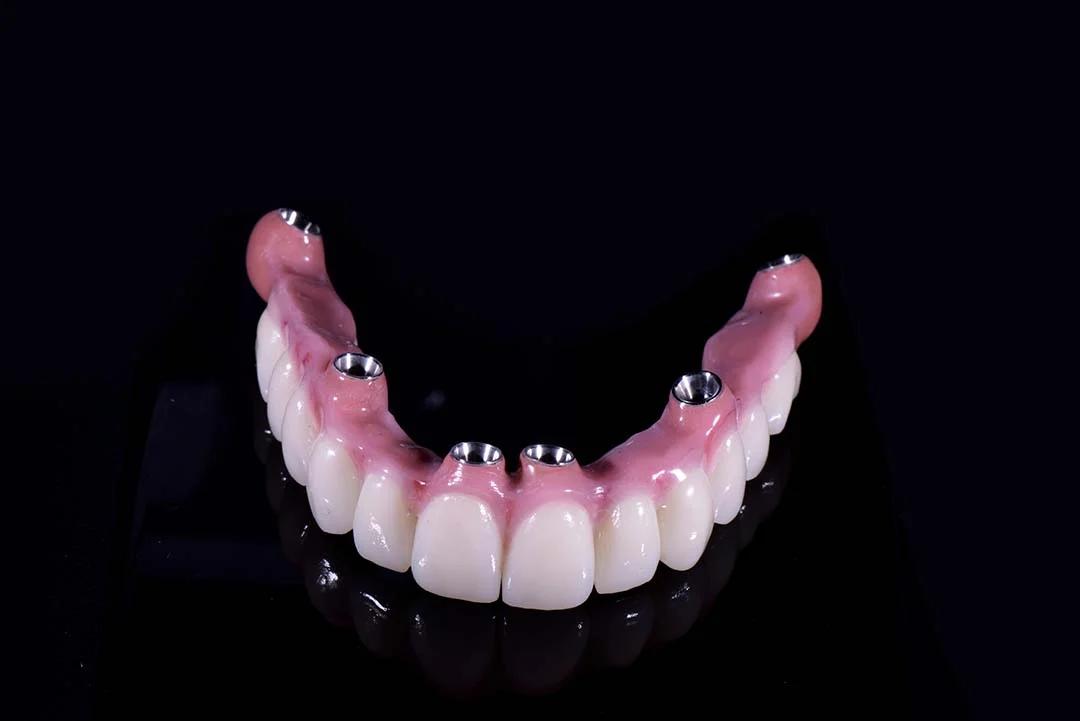

- Oltre a permettere l’inserimento di protesi fisse complete fino a 14 denti, questi impianti sono spesso impiegati in combinazione con impianti tradizionali o zigomatici, nell’ambito di protocolli a carico immediato, dove il paziente riceve i denti fissi entro 24-48 ore dall’intervento.

Uno dei maggiori benefici è la possibilità di posizionare la protesi provvisoria fissa entro 24 ore dall’intervento, riducendo drasticamente i tempi di trattamento. Grazie all’elevata stabilità primaria garantita dalla densità ossea della zona pterigoidea, è possibile procedere con un carico immediato, ovvero applicare i denti fissi lo stesso giorno o il giorno dopo l’inserimento degli impianti. - Permettono la riabilitazione completa con arcata lunga

A differenza delle tecniche All-on-4 e All-on-6 che spesso si limitano a 10 o 12 denti, gli impianti pterigoidei consentono di riabilitare l’intera arcata superiore con 14 denti fissi, inclusi i molari, per una masticazione completa ed efficace. - Riduzione significativa dei tempi complessivi di trattamento